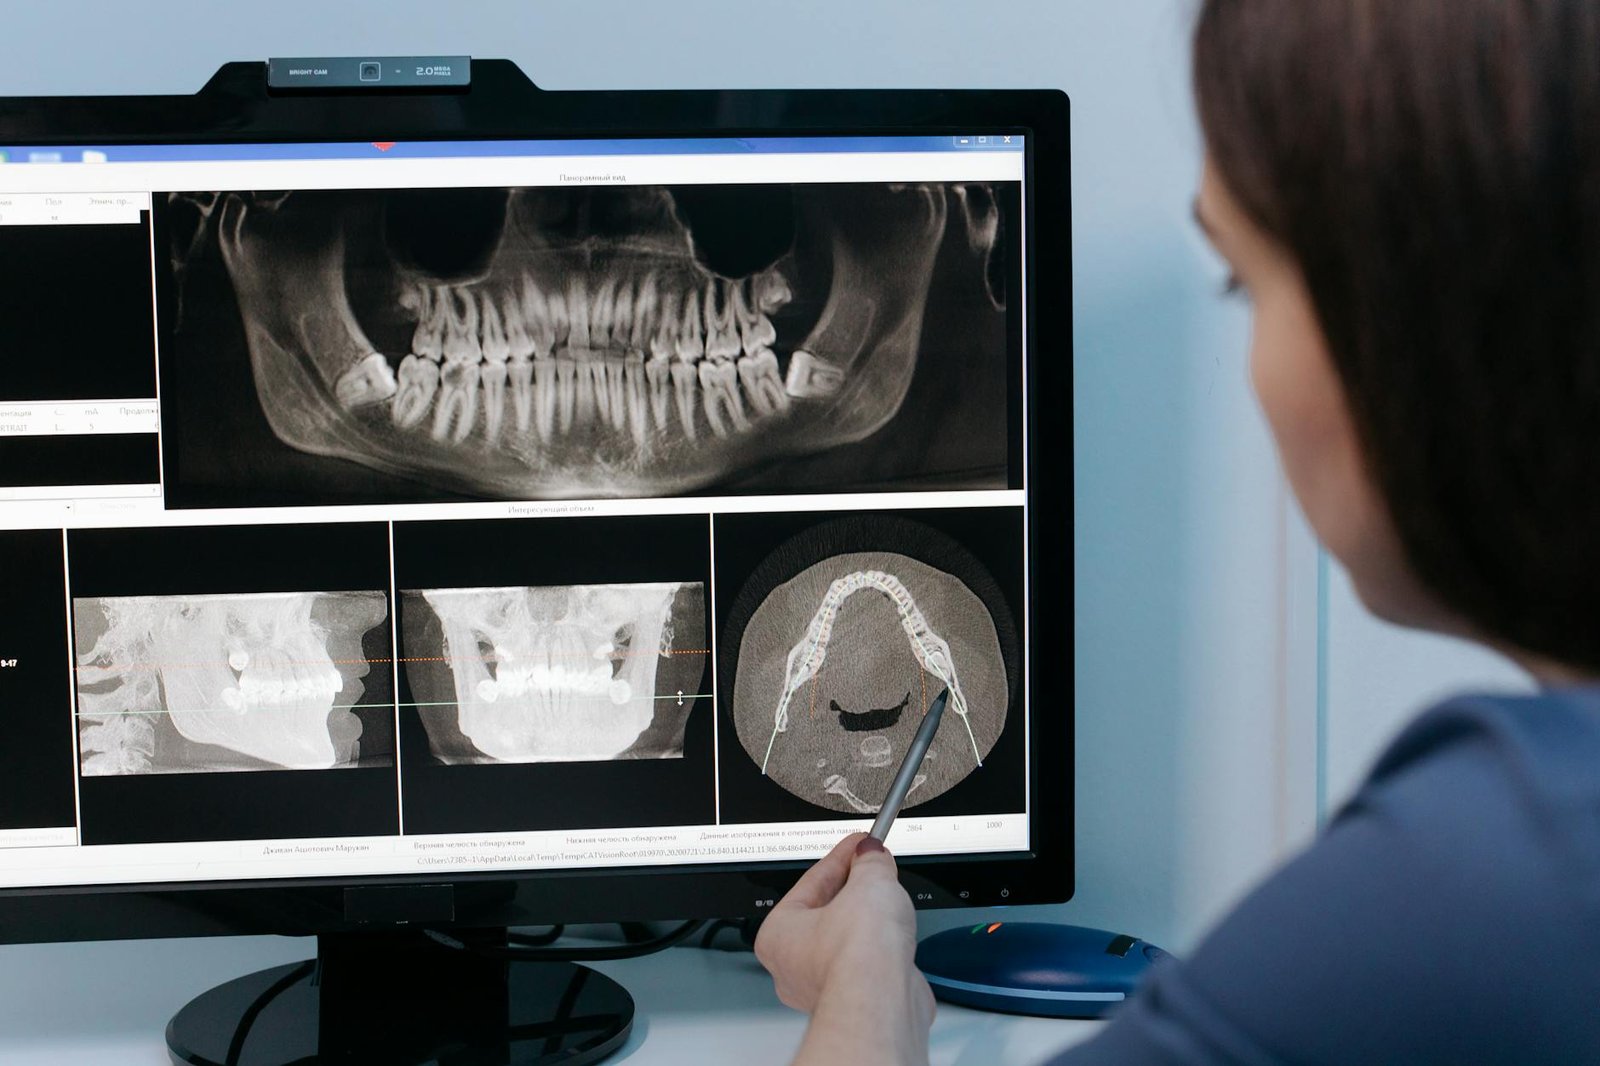

Cone beam CT imaging transforms the way dental professionals approach diagnosis by delivering complete three-dimensional visualization of oral and maxillofacial structures. Unlike conventional radiographs that compress anatomical structures into flat, two-dimensional images, CBCT provides volumetric data that can be manipulated and viewed from multiple angles and planes.

The technology works by rotating a cone-shaped X-ray beam around the patient’s head, capturing hundreds of individual projection images during a single scan. These images are then reconstructed by sophisticated software algorithms to create detailed cross-sectional views in axial, sagittal, and coronal planes. This comprehensive approach allows practitioners to examine structures that might be obscured or overlapped in traditional radiographic images.

CBCT’s ability to generate real-time cross-sectional views revolutionizes treatment planning accuracy across multiple dental specialties. The technology provides immediate access to axial, sagittal, and coronal sections, allowing practitioners to evaluate anatomical relationships and pathological conditions from multiple perspectives during patient consultations.

Implant treatment planning exemplifies CBCT’s real-time advantages most dramatically. Practitioners can measure bone dimensions, evaluate bone quality, and identify critical anatomical structures like the inferior alveolar nerve or maxillary sinus in real-time during the planning session. Interactive software allows for virtual implant placement, enabling clinicians to optimize positioning, angulation, and depth before surgery begins. This real-time capability reduces surgical time, improves outcomes, and enhances patient confidence through visual treatment presentations.